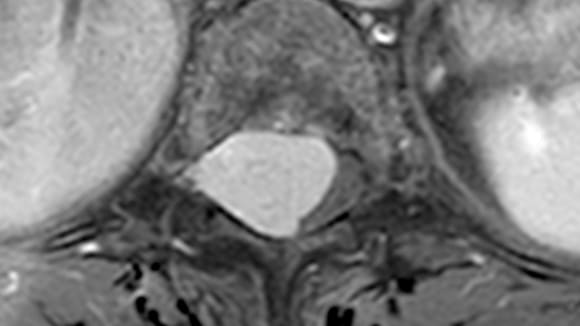

Les tumeurs intra-durales, situées à l’intérieur du sac méningé qui renferme le système nerveux central, représentent un défi médical majeur. Les principaux types de tumeurs affectant cette zone sont les méningiomes et les neurinomes, nécessitant une expertise neurochirurgicale de haut niveau. La chirurgie intra-durale rachidienne est reconnue pour sa complexité et ses risques élevés, exigeant la présence de deux neurochirurgiens, un microscope opératoire et des instruments de microchirurgie.

Cette avancée permet désormais de réaliser des chirurgies intra-durales des tumeurs thoraciques et lombaires à Narbonne, offrant ainsi aux patients une prise en charge locale et évitant les déplacements hors de la région.